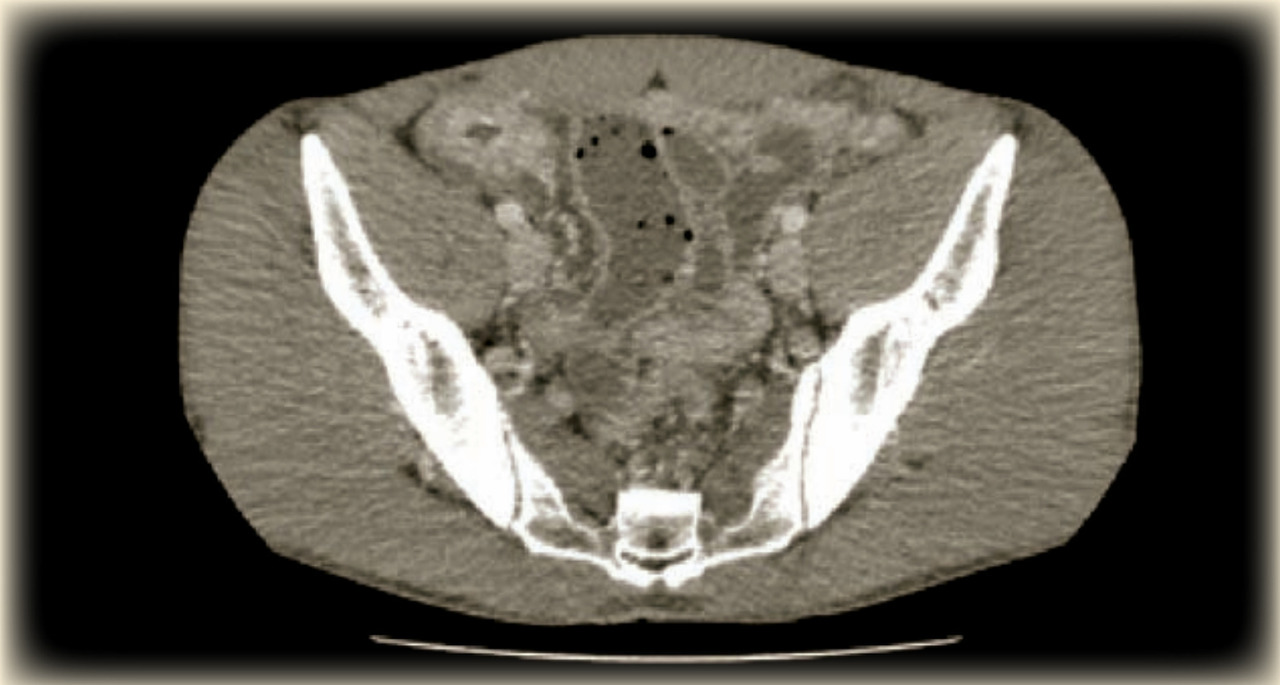

Voici les résultats du scanner abdomino-pelvien réalisé à la demande de son médecin traitant :